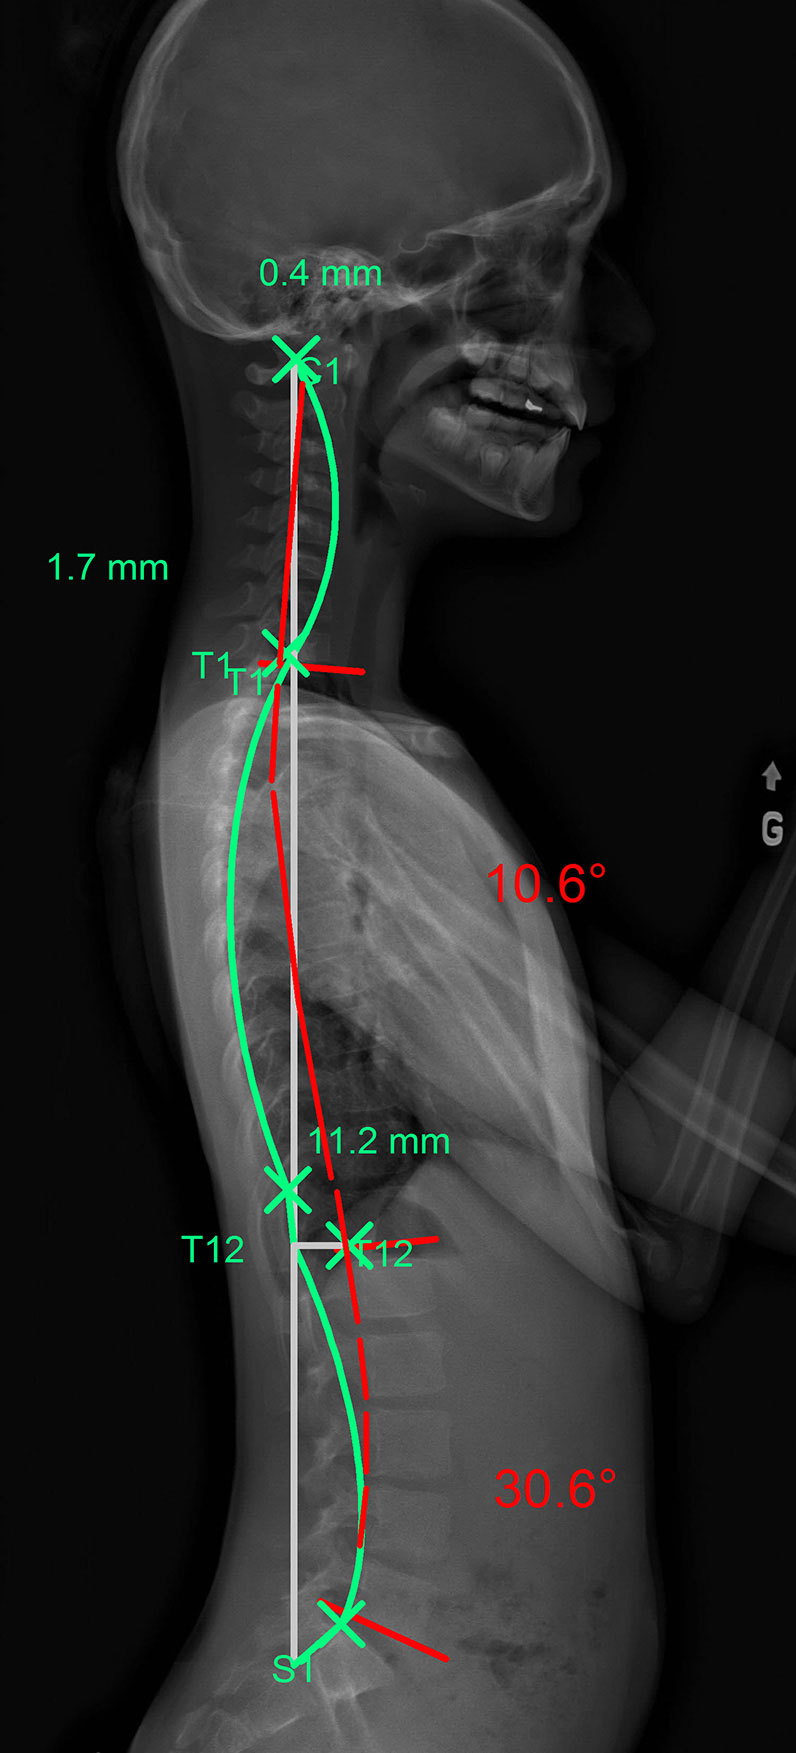

Hyperkyphosis can affect different portions of the thoracic spine as shown in these images (the green line represents an ideal spine, the red line represents the patient’s abnormal kyphotic curvature):

The green line represents the ideal spinal curvature and the red line that of the patient’s spine in profile view.